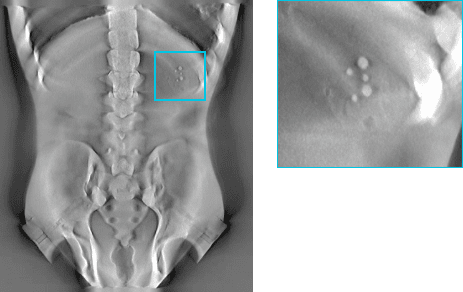

흉부 Lungman Phantom

Before

After

4343 + Linear Motion: Lungman

4360(대면적): Lungman